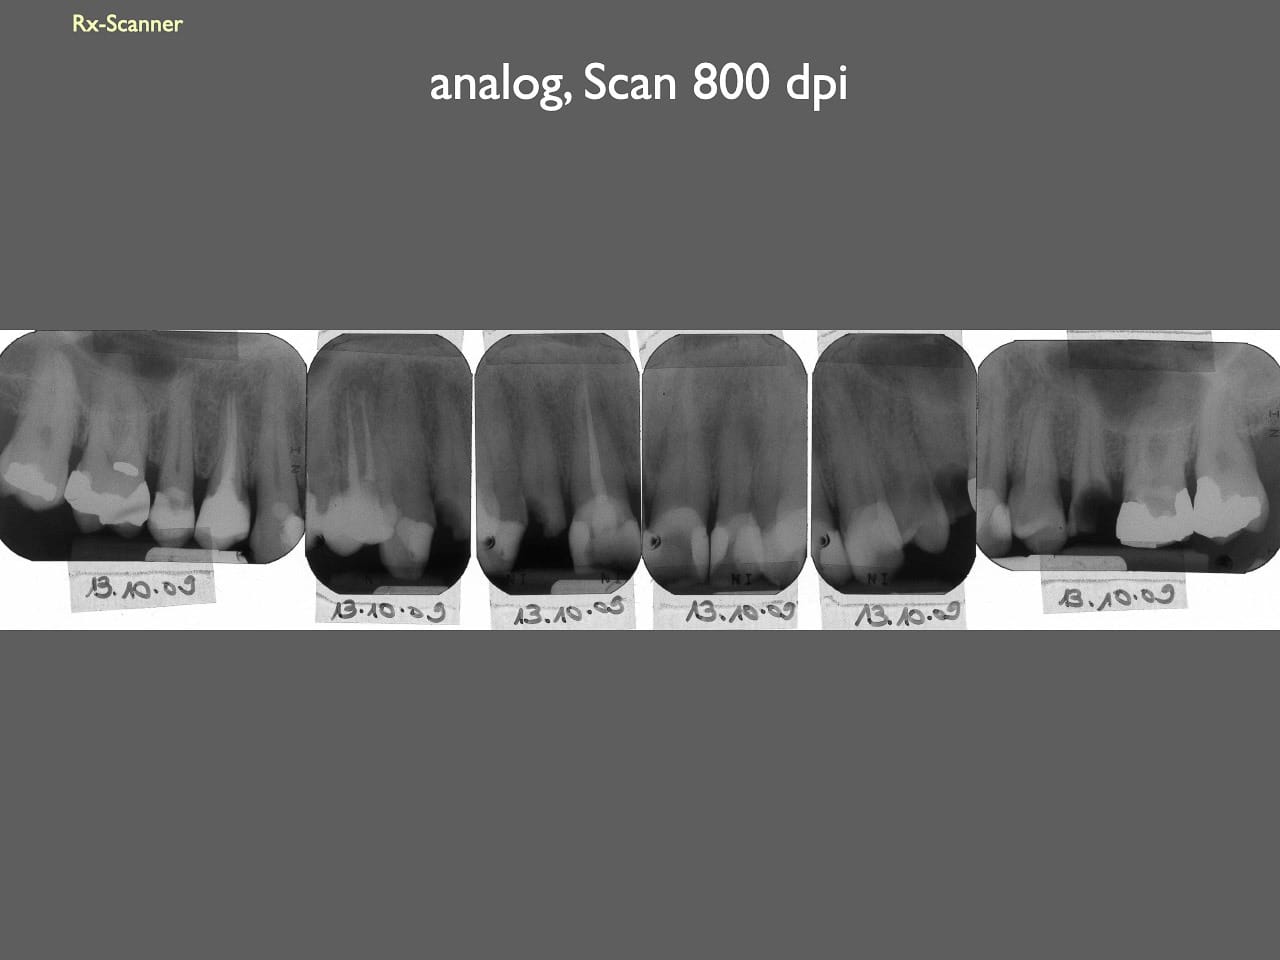

dental Scannen in der Zahnarztpraxis. Study Club vom 28.2.2010. Von peter portmann, Veröffentlicht am 28. Feb. 2010 — 3 min Lesezeit dokumentationfoto Auf dieser Seite Zahnarztpraxis-Trilogie zu Fotografie und Dokumentation Portrait Fotografie Scannen Scannen